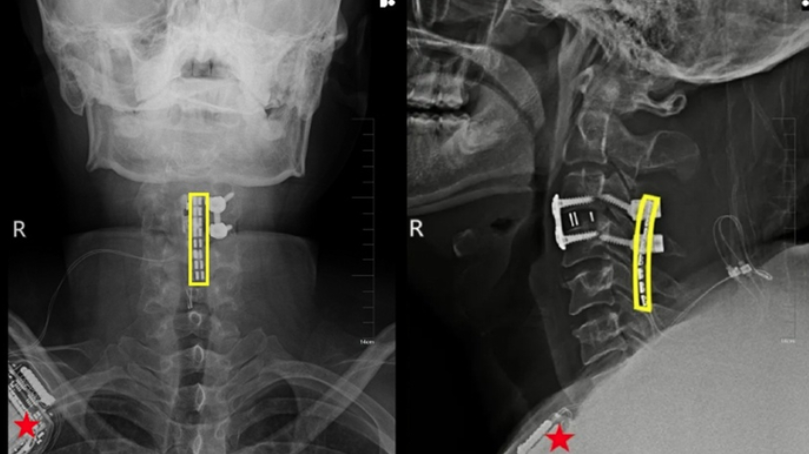

據稱,頸脊髓損傷患者的大腦和脊髓的聯繫完全中斷,而「脊髓介面技術」是指在損傷部位,精準植入微型電極裝置,透過對肢體運動神經元的啟動與控制,讓患者能夠重新支配癱瘓肢體自主活動。

經過兩周不斷改良的精准神經調控,劉博奇四肢肌力顯著恢復。3個月後,團隊為他度身定造「脊髓介面+外骨骼機器人」康復方案。在脊髓介面的精准調控以及外骨骼輔助下,劉博奇成功邁出受傷後的第一步,成為世界首宗運用脊髓介面技術,令四肢高位截癱者恢復自主活動的案例。